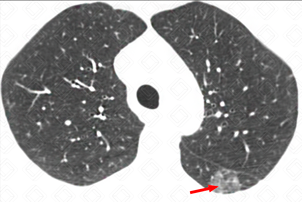

Texto alternativo para a imagem Figura 3. Créditos: Dra. Elazir Mota - Rio de Janeiro/RJ

Descrição das figuras 1, 2, 3 e 4: Tomografia computadorizada do tórax, seguida de reconstruções axiais e sagitais. Massa pulmonar, com contornos espiculados, localizada no segmento apical do lobo superior direito, medindo 3,2 cm x 1,5 cm x 2,2 cm (setas vermelhas).

Lembrando que, acima de 3 cm, a lesão já deve ser descrita como massa. Lesões menores que 3 cm são descritas como nódulos. Isso também é importante no estadiamento TNM (lesões ≥ 3 cm já são consideradas pelo estadiamento como T2).